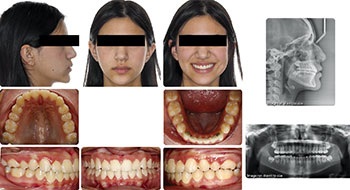

The first case is a 12-year-old female. Initially, the significant lingual inclination of her posterior teeth led me to believe that dental arch expansion would provide enough arch length to satisfy my non-extraction treatment plan. I didn’t invert upper incisor brackets as I didn’t think much negative torque would be needed after that expansion. However, her smiling side profile and the mid-treatment ceph from the pan/repo/ceph appointment at five months surprised me with the extent of the upper incisor proclination. At that point in treatment, I understood that a pivot was needed, and I felt confident that the appropriate use of negative torque and IPR would position her upper incisors where I wanted them to be within her face and smile. I decided to flip the upper incisor brackets at that same visit and progress with treatment, including IPR and engagement of the negative torque at subsequent appointments. She completed treatment in 18 months, achieving a favorable position of her upper incisors in her face and smile.